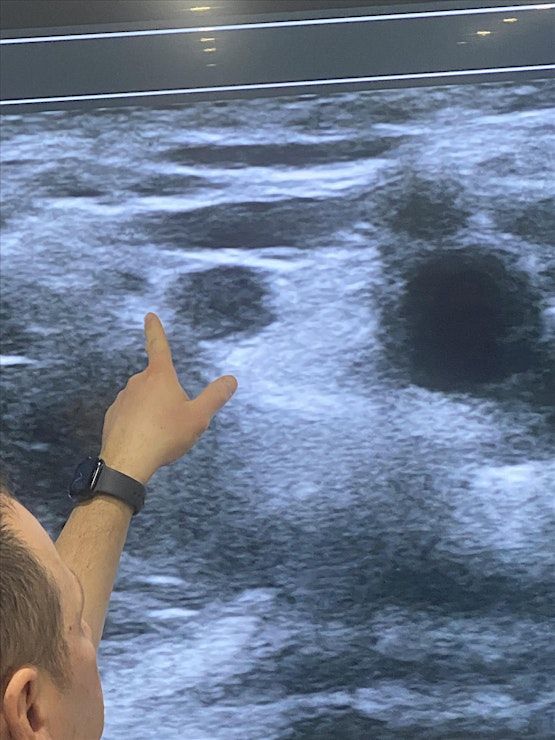

This 1 day intensive workshop has been developed for both novices and advanced pain physicians providers who would like to either learn the basics or further advance their skills in ultrasound guided pain procedures and regional anesthesia. Participants will have up to 6 hours of hands on ultrasound scanning on live models and lecture to learn and identify different sono‐anatomy. At the end of the workshop, you will be expected to have gained thorough knowledge and immense confidence in the use of ultrasound for pain procedures

• Identify normal sono‐anatomy and aberrations

• Increase the ability to detect critical structures and improve patient safety while performing pain procedures

• Perform nerve block | epidural and large joint imaging with ultrasound

Scanning Live Models for Ultrasound Guided Joint Injections & Nerve Blocks